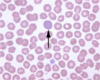

What is shown in this picture?

arrow pointing at an example of polychromasia

note the grey blue cell without central pallor

this implies the presence of reticulocytes

some people say you need to correct the reticulocyte count for polychromasia by dividing it by 2.